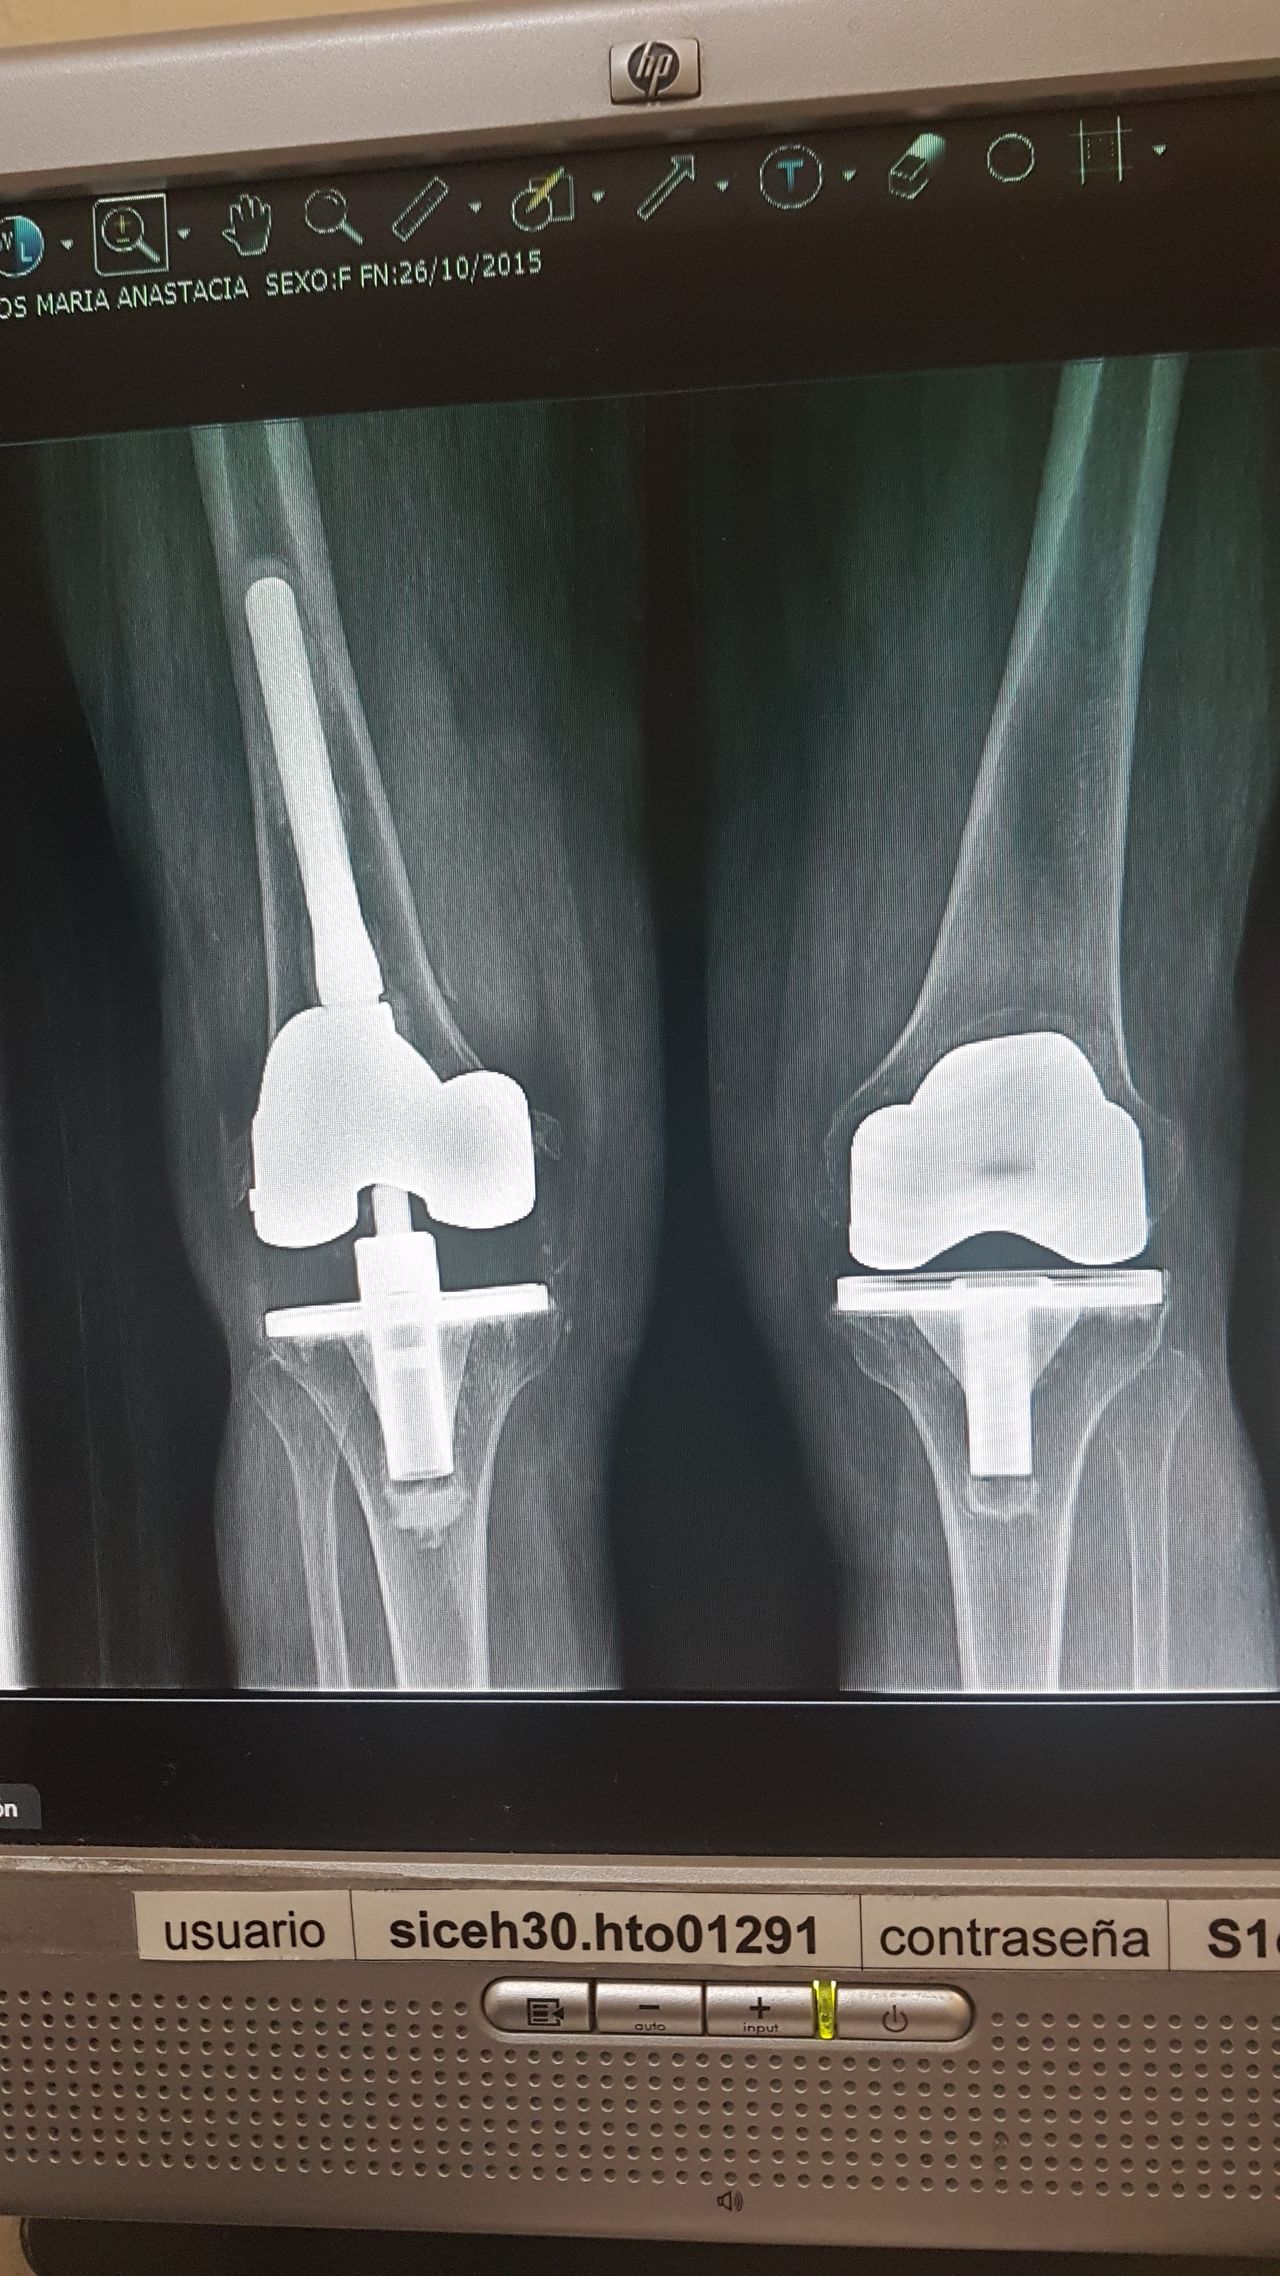

Soy   egresado  de  la  Universidad Autonoma de   Nuevo  Leon. especialidad de ortopedia y traumatologia  en    hospital  numero  21  del  IMSS ne Monterrey  N.L ,con entrenamiento en la  subespecialidad  de   reconstrucion  articular  y  artroscopia  que incluye  lesiones  de  meniscos  , reconstruccion de ligamentos cruzados , lesiones  condrales ,  gonartrosis   tengo  una  historia laboral    institucional de 30  años    hasta el 30  de lulio del 2024 estuve  10  años  en  el  modulo  de  artroscopia  con aproximadamente   1120    artroscopias  de rodilla   y  15 años  en  el  departamento  de    artroplastia  de rodilla  o  de  reemplazos  articulares   ,  los  ultimos   15  años    como profesor  adjunto   y titular  en los cursos    de pre  y posgrados  de  traumatologos  en la  subespecialidad  de  con aproximadamente   160 cirugias  institucionales    en   artroplastia de  rodilla    por  cada año   y  un  numero menor en el  medio particular  dando un total  aproximado  de  2,560  cirugias . de  estas  el  10%    de  revision  y  5%  preotesis    tumorales    de  actualmente   en  funciones  en  el  medio privado  y  acreditado  en todos los  hospitales  de la  localidad  y  con todas  las  aseguradoras   de  gastos  medicos .